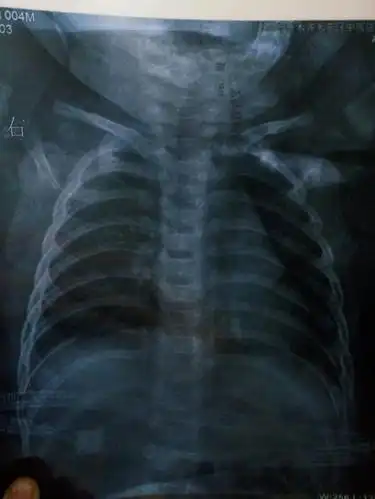

小孩两个月了,不发烧,偶尔咳两下,拍片子诊断为支气管肺炎,医请各位